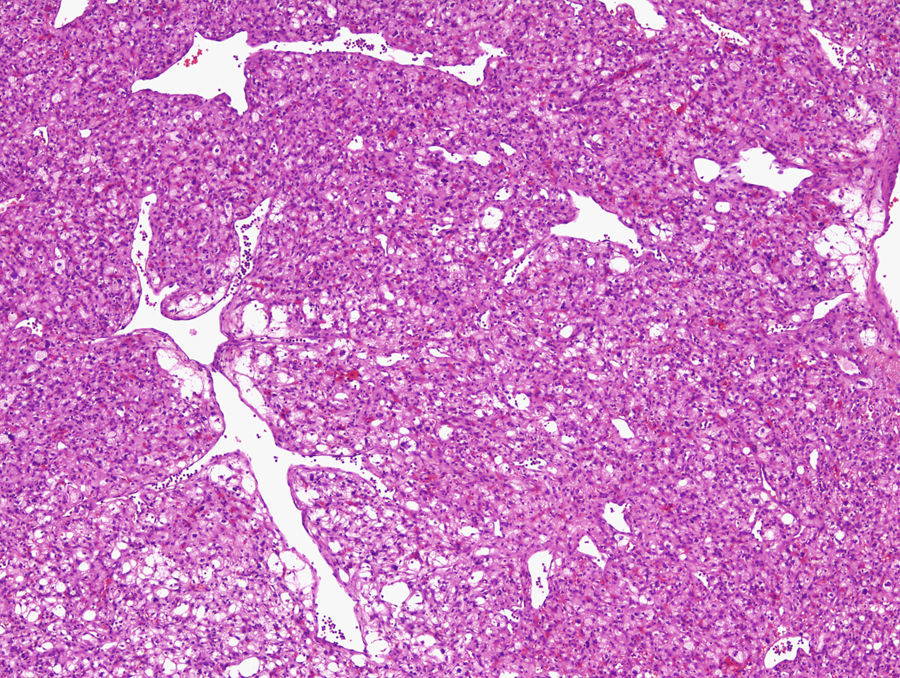

Mujer de 38 años con poliglobulia y una masa abdominal

A 38-year-old woman with polyglobulia and a abdominal mass